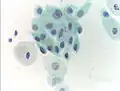

Micrograph of a normal pap smear -

Normal squamous epithelial cells in premenopausal women -

Atrophic squamous cells in postmenopausal women